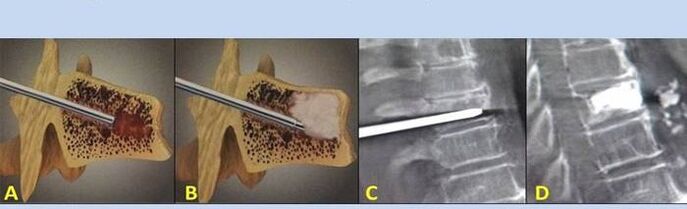

- Nucleoplastica – rimozione del nucleo del disco intervertebrale. L'operazione allevia la pressione sulle terminazioni nervose.

- Vertebroplastica con puntura – metodo di stabilizzazione delle vertebre. Durante la procedura, il medico riempie le cavità della colonna vertebrale con cemento osseo.